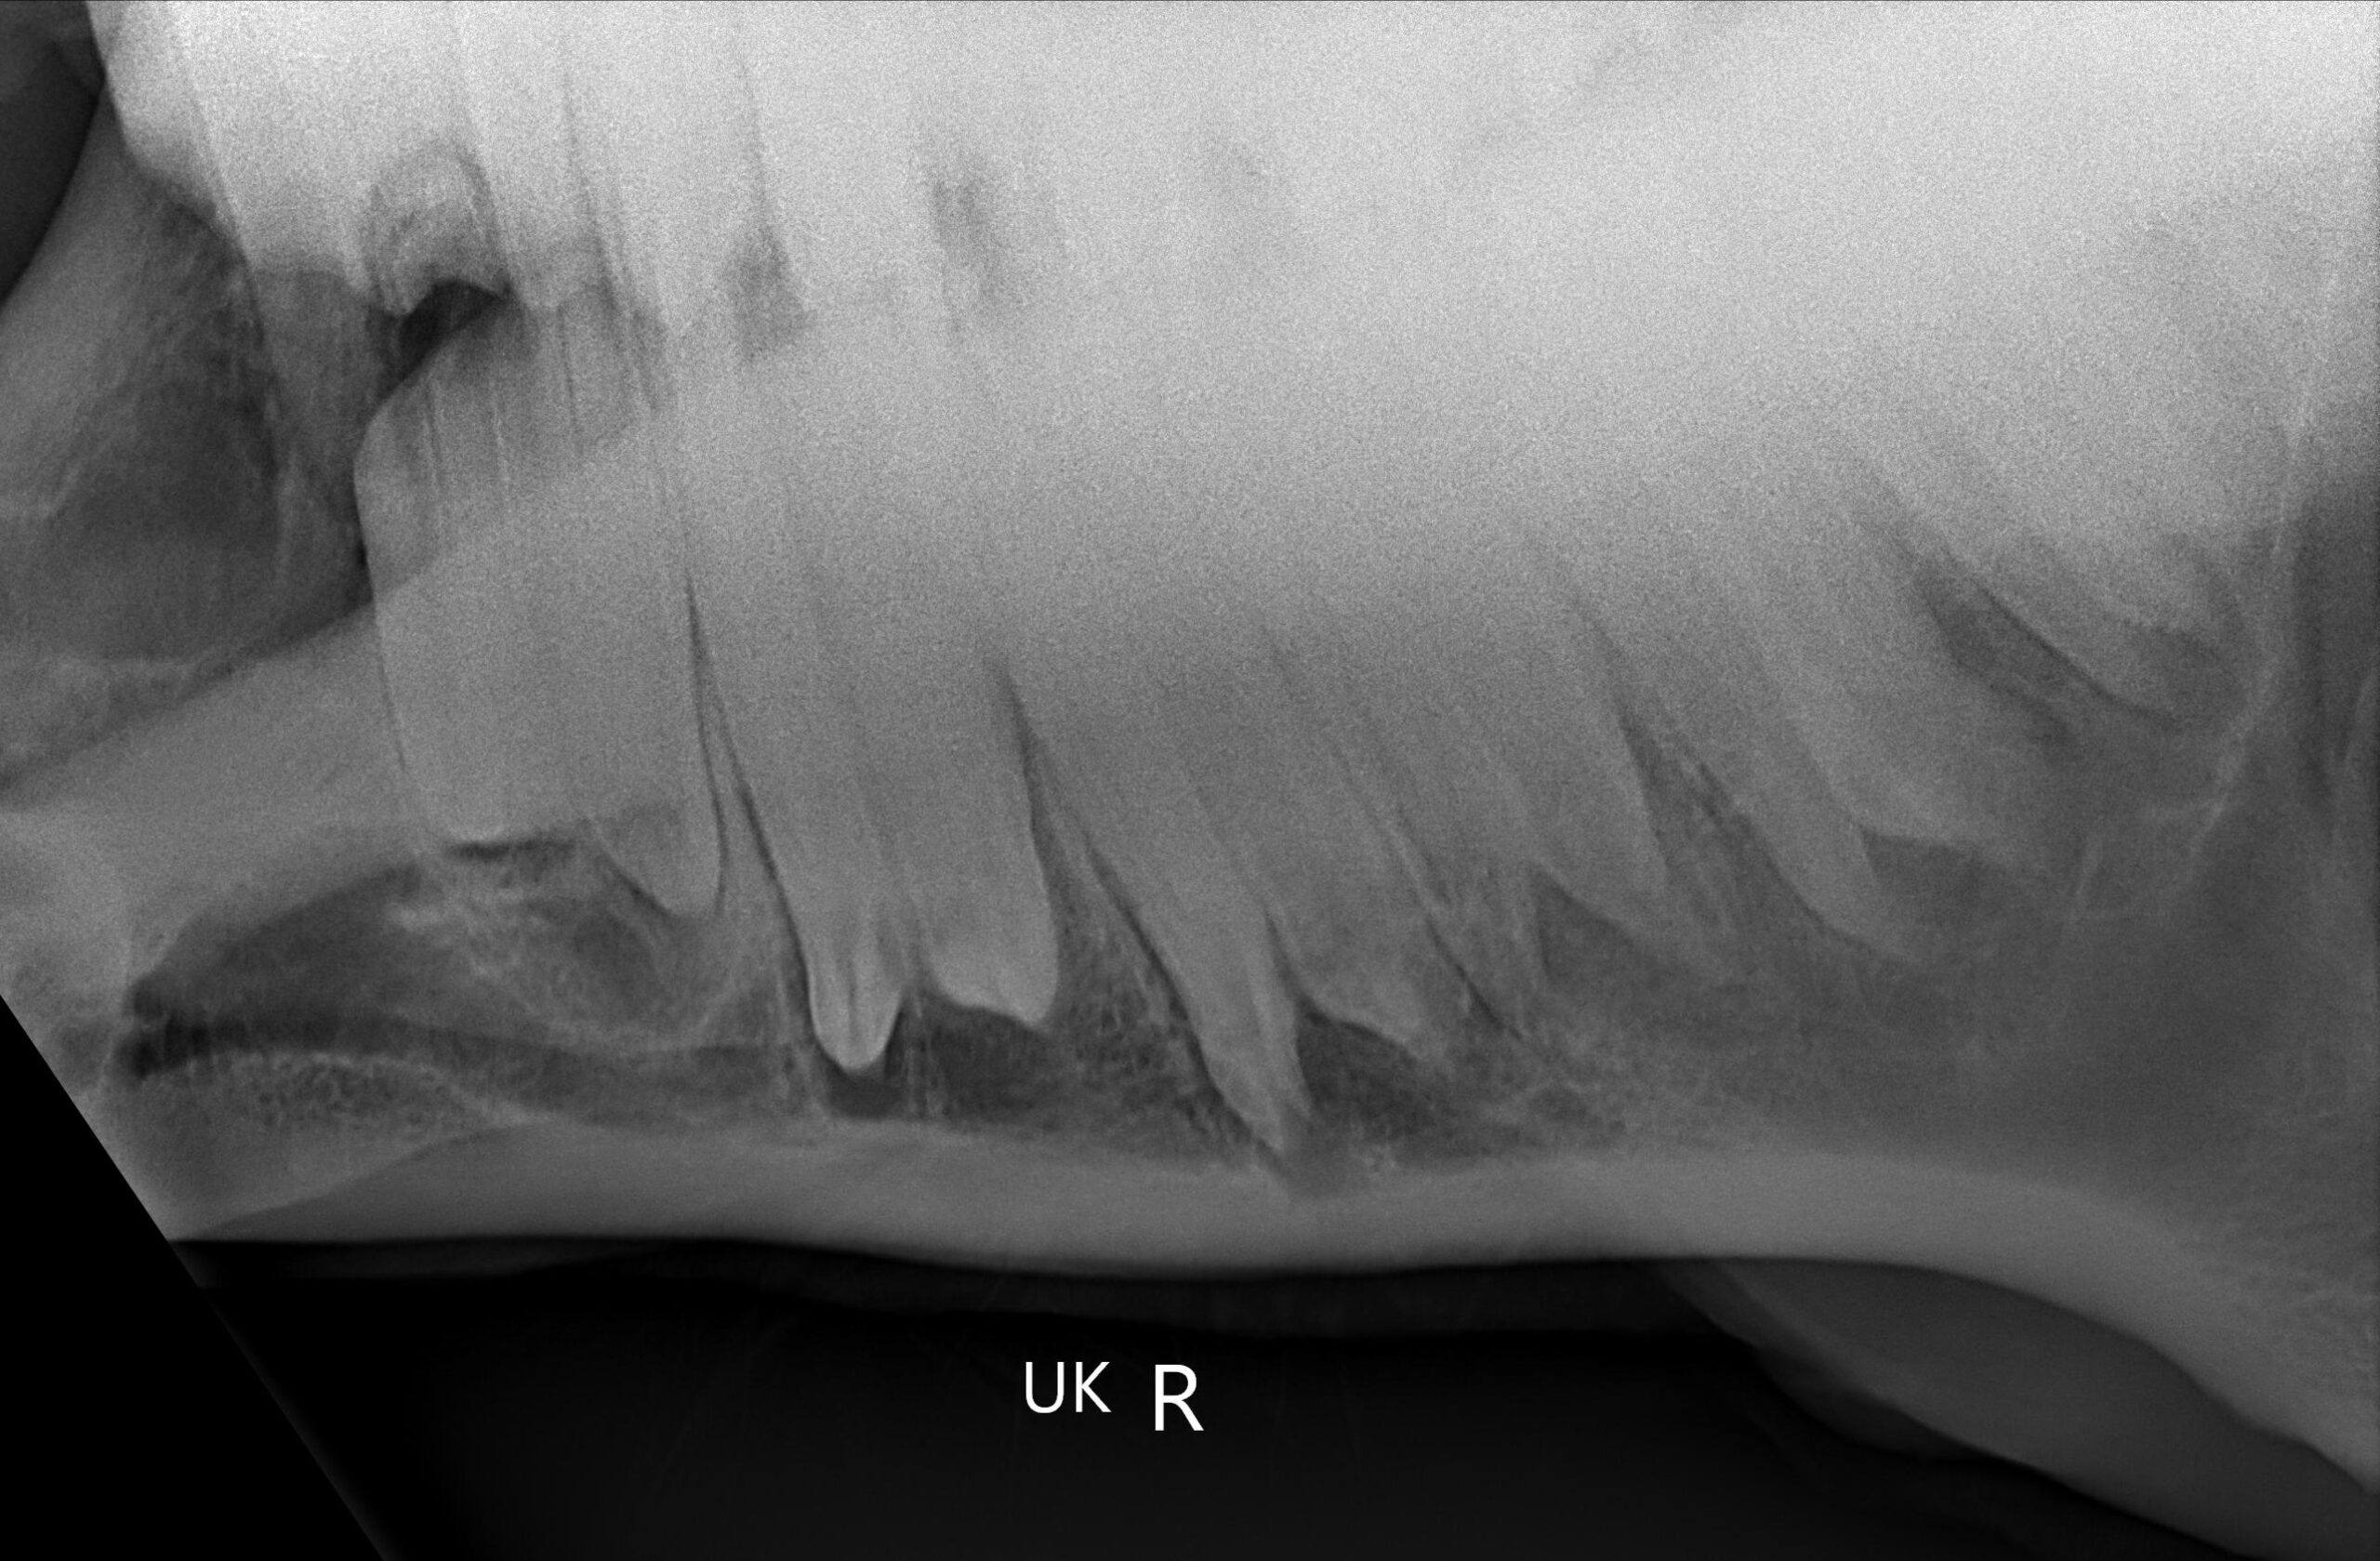

Zur weiteren Diagnostik bei größeren Problemen steht uns ein mobiles Röntgen zur Verfügung. In der Klinik ermöglicht das Maulhöhlenendoskop zusätzlich einen guten Einblick auf schlechter einsehbare Bereiche und der Tierarzt kann anhand der Bilder auf dem Monitor sehr gut die jeweiligen Befunde zeigen und den weiteren Plan gemeinsam mit dem Besitzer erläutern.